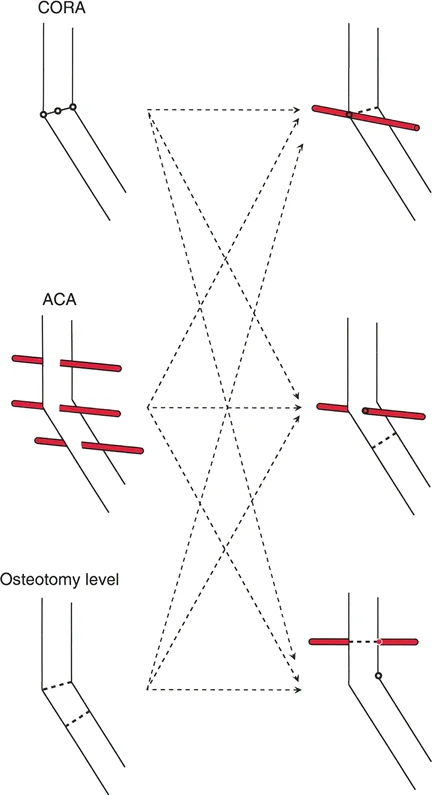

* تحديد المحور الميكانيكي: رسم الخطوط التي تحدد المحور الميكانيكي للطرف بدقة.

* قياس الزوايا: قياس الزوايا المختلفة للمفاصل (مثل زاوية الفخذ الوحشية القريبة mLPFA وزاوية الفخذ الوحشية البعيدة mLDFA) ومقارنتها بالقيم الطبيعية.

* تحديد موقع مركز دوران الانحراف (CORA): وهو نقطة التقاطع بين محاور العظم القريبة والبعيدة، والتي تمثل قلب التشوه.

مركز دوران الانحراف (CORA)

يعتبر CORA خاصية أساسية للتشوه في العظم. يُعرّف بأنه نقطة تقاطع خط المحور الميكانيكي (أو التشريحي) القريب وخط المحور الميكانيكي (أو التشريحي) البعيد.

بينما يعتبر CORA حقيقة تشريحية ثابتة، فإن ACA يقع جزئيًا تحت سيطرة الجراح. يمثل ACA النقطة المحورية التي يدور حولها الجزء البعيد من العظم لتحقيق التصحيح.

* الموضع الأمثل: يجب أن يكون ACA موجهًا بشكل عمودي على مستوى التشوه ويمر مباشرة عبر CORA.

القاعدة الذهبية الأولى: القطع والمفصلة عند مركز الانحراف

عندما يمر كل من قطع العظم وACA مباشرة عبر CORA، يتم تصحيح التشوه الزاوي بشكل مثالي. يتم استعادة المحور الميكانيكي، ولا يوجد انحراف في المحور الميكانيكي (MAD)، وتبقى أجزاء العظم القريبة والبعيدة متوازية تمامًا. هذا هو السيناريو المثالي، والذي غالبًا ما يتحقق بقطع عظم وتدي بسيط (فتح أو إغلاق) عند قمة التشوه.

القاعدة الذهبية الثانية: المفصلة عند مركز الانحراف والقطع بمستوى مختلف

في بعض الأحيان، قد يكون قطع العظم مباشرة عند CORA غير ممكن سريريًا بسبب سوء حالة الجلد، أو وجود أدوات جراحية سابقة، أو مشاكل في جودة العظم في منطقة الكردوس/الجذع. إذا بقي ACA عند CORA، ولكن تم إجراء قطع العظم عند مستوى مختلف (أقرب أو أبعد عن CORA)، فسيتم تصحيح التشوه الزاوي بالكامل. ومع ذلك، ستنزاح نهايات العظم عند موقع قطع العظم بالنسبة لبعضها البعض.

* النتيجة السريرية: يؤدي هذا إلى "نتوء" أو تعرج في المحور التشريحي، لكن المحور الميكانيكي العام وتوجيه المفصل يظلان متوائمين تمامًا.